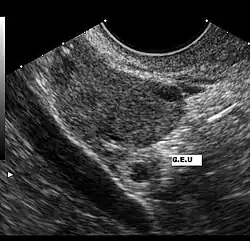

L'échographie par sonde abdominale permet de visualiser une masse hétérogène latéro-utérine, constitué par le sac gestationnel en dehors de la cavité utérine. L'utérus est vide mais ses parois épaissies. Un épanchement au niveau du cul-de sac de Douglas peut être mis en évidence. Cet examen a une très bonne sensibilité pour le diagnostic mais une spécificité moins importante[8].

Des β-HCG supérieurs à 4000 UI/l sans visualisation du sac ovulaire intra-utérin signent pratiquement la grossesse extra-utérine.

L'examen échographique peut être complété par l'utilisation d'une sonde endovaginale, permettant de mieux visualiser trompes, ovaires et contenu utérin et d'avoir une précision diagnostique plus importante[9].